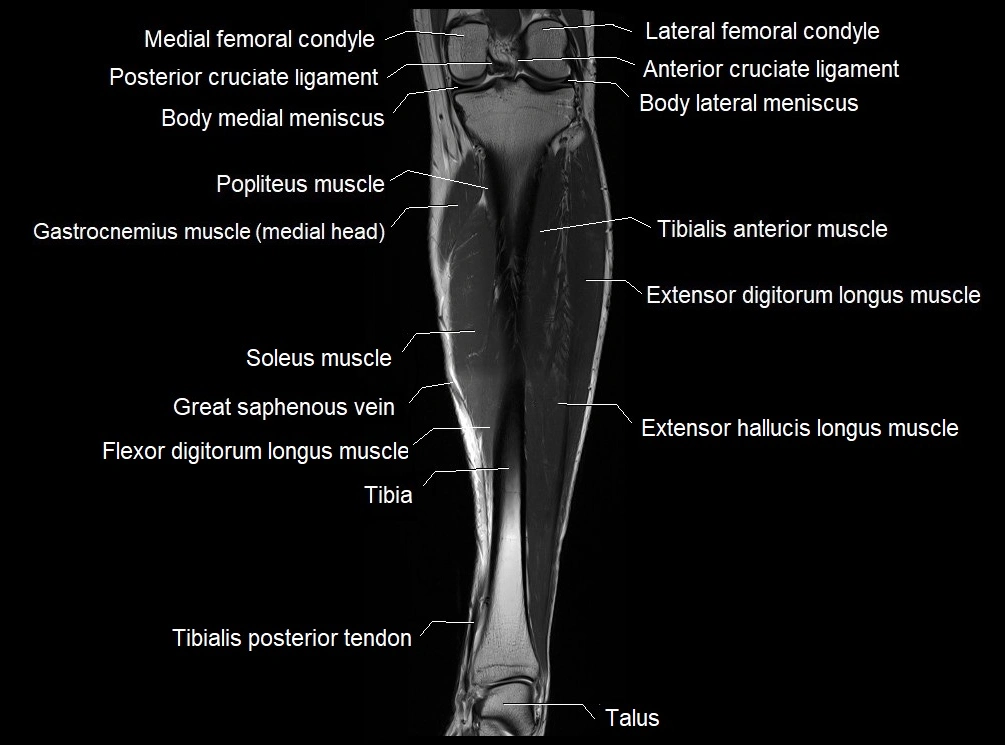

MRI image